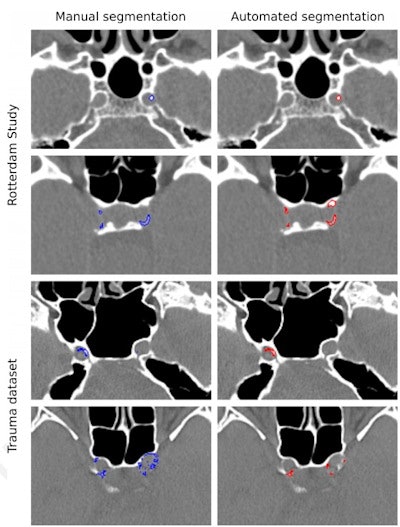

Examples of manual and automated segmentations of Rotterdam Study and trauma dataset scans. The images shown were preprocessed. Trauma dataset images were additionally smoothed with a Gaussian filter to make them more similar to Rotterdam Study scans used for training and thus improve the method's performance. Images and caption courtesy of the RSNA.For identifying ICAC, the deep-learning algorithm showed a sensitivity of 83.8% and a positive predictive value of 88%. Correlation between manually performed and automated ICAC volume measures was 0.98. The researchers also found a strong association of ICAC volume with stroke for both automated and manually measured volumes, with hazard ratios of 1.38 and 1.48, respectively.